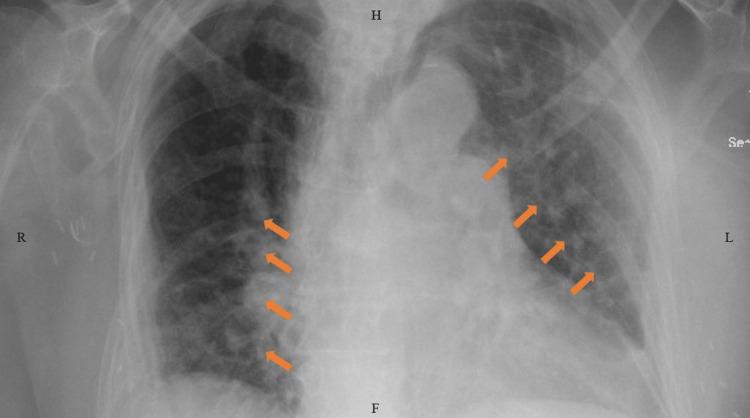

()and coronavirus disease 2019 (COVID-19) infections can have overlapping symptoms. Recently, the association and outcomes of coinfection have been studied. We present the case of an 83-year-old lady with Parkinson's disease (PD) who was admitted with pneumonia secondary to severe acute respiratory syndrome coronavirus-2 (SARS-CoV-2) infection. She was treated with empiric antibiotics ampicillin-sulbactam and azithromycin, along with antiviral therapy remdesivir and baricitinib, and dexamethasone. The patient developed severe infection with a leukemoid reaction. She was treated with intravenous metronidazole and oral vancomycin without any improvement. Before she could receive a fecal microbiota transplant, her infection progressed to fulminant colitis, and she required emergent surgery. The patient developed several complications post-surgery and succumbed to the severe illness. Our patient's multiple comorbidities and an underlying COVID-19 infection predisposed her to severe illness. This case emphasizes the long-standing discussion on antibiotic stewardship and encourages a debate on the role of immunosuppressant antiviral medications and underlying PD in predisposing patients to a severe infection.

()与2019冠状病毒病(COVID-19)感染可能有重叠症状。最近,已对合并感染的关联和结果进行了研究。我们报告一例83岁帕金森病(PD)女性患者,因严重急性呼吸综合征冠状病毒2(SARS-CoV-2)感染继发肺炎入院。她接受了经验性抗生素氨苄西林-舒巴坦和阿奇霉素治疗,同时接受了抗病毒治疗瑞德西韦和巴瑞替尼以及地塞米松治疗。患者发生了严重感染并伴有类白血病反应。她接受了静脉注射甲硝唑和口服万古霉素治疗,但无任何改善。在她能够接受粪便微生物群移植之前,感染进展为暴发性结肠炎,她需要紧急手术。患者术后出现了多种并发症,最终死于重症。我们患者的多种合并症和潜在的COVID-19感染使她易患重症。该病例强调了关于抗生素管理的长期讨论,并鼓励就免疫抑制性抗病毒药物和潜在的帕金森病在使患者易患严重感染方面的作用展开辩论。